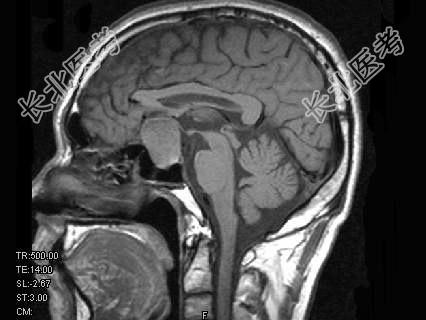

- 单项选择题男,49岁, 1年前发现双颞侧视野缺损,视物模糊, 查体:双颞侧偏盲, 根据所提供图像,最可能的诊断为 ( )

A、垂体微腺瘤

B、颅咽管瘤

C、脑膜瘤

D、嫌色细胞腺瘤

E、生殖细胞瘤